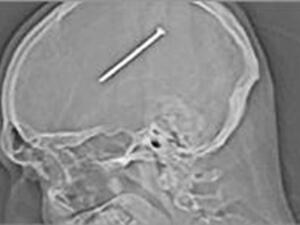

المسمار داخل الراس

22 يناير 2012 - 09:50 GMT

دخل مسمار طوله 8 سنتميترات في رأسه دون ان يشعر به!